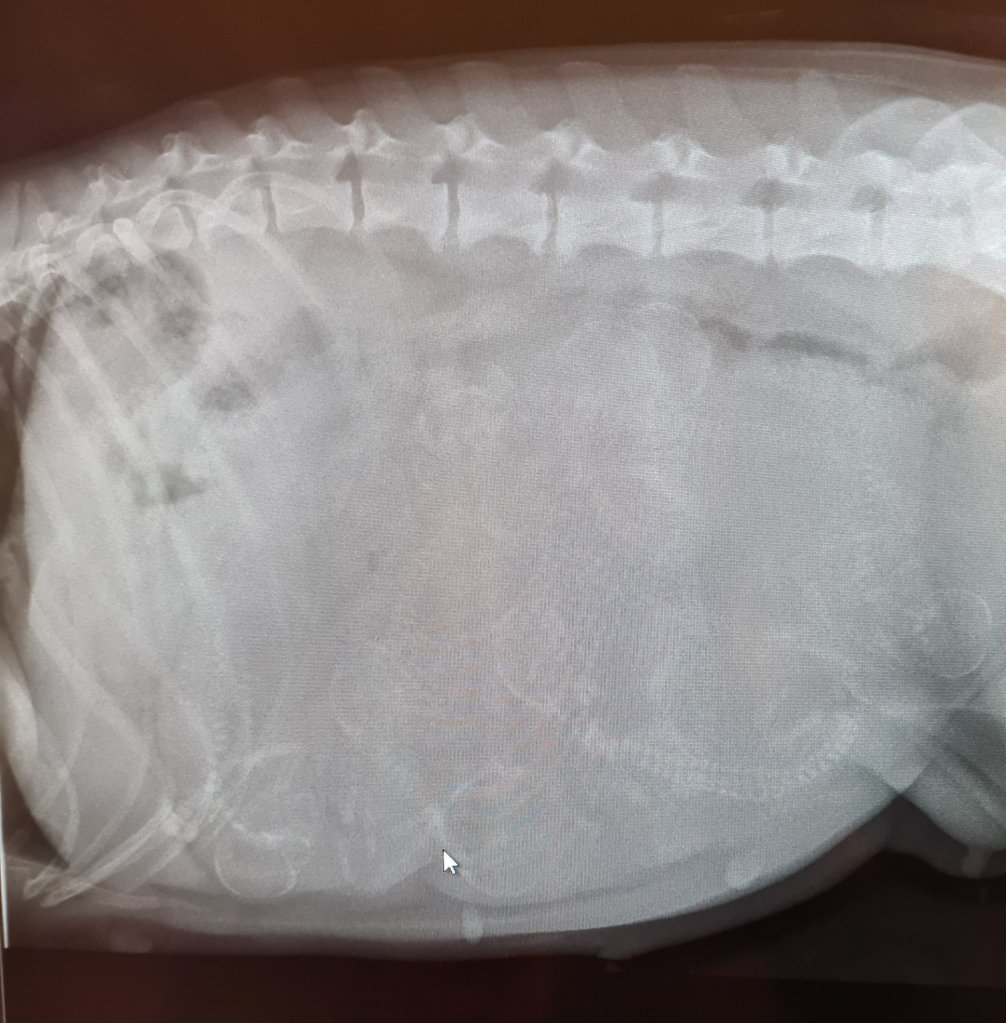

Idag har vi varit på röntgen med Naja. Hon var jätteduktig och lå still.

Och hur många valpar är det då? Jo helt säkert 7, troligen 8 och kanske kan det finnas 9. Två veterinärer och en assistent kollade, ni kan ju testa och räkna lite själva 😅

Naja mår bra, veterinären tyckte hon var i bra lagom hull. Juvren är stor och börja förbereda sig för produktion.